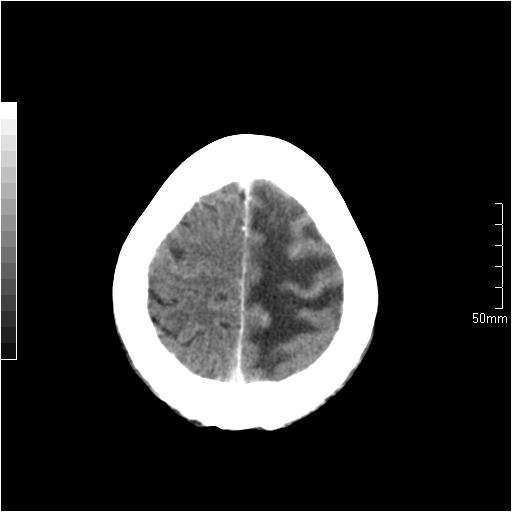

以下是引用天南地北在2007-6-25 12:39:00的发言:[br]有占位效应[br]支持术后复发

以下是引用zjzjr在2007-6-25 12:38:00的发言:[br]左侧复发,右侧转移。